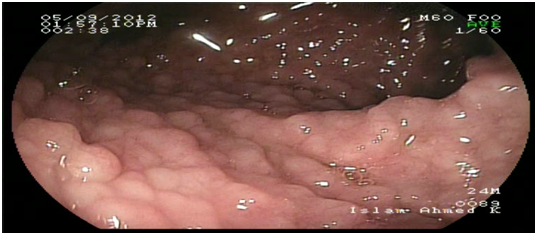

Abdominal ultrasound showed uniform circumferential mural thickening of the small bowel loops, so we proceeded to C.T Enterography. As shown in Figure 1, there is diffuse uniform thickening of the small bowel loops mainly involving the ileum with no focal thickening or masses. Then upper endoscopy and colonoscopy were performed to the patient and they showed multiple tiny rounded nodules at the terminal ileum that were biopsied and revealed non-specific inflammation free of granuloma or malignancy. Then we proceeded to double balloon enteroscopy which was done by an over tube double balloon Fuji series endoscopy, which proceeded to about 200cm from the duodenal bulb. Double balloon endoscopy as shown in Figure 2, showed numerous visible mucosal nodules measuring few millimeters in diameter involving the whole part of the small intestine examined which were biopsied. Histopathology revealed chronic inflammatory enteritis with foci of lymphoid aggregates with no atypia or malignancy (Table 1).

Figure 2 Diffuse small nodules scattered through the whole small intestine by double ballonenteroscopy.

Some reports had described DNLH in adult patients without immunodeficiency and it was thought to be associated with chronic GIT infections such as Giardiasis or Helicobacter pylori infection.4,8,10 Nodular lymphoid hyperplasia generally presents as an asymptomatic disease, but it may cause gastrointestinal symptoms like abdominal pain, chronic diarrhea, malabsorbtion syndrome, bleeding or very rarely intestinal obstruction.5 One of the most important issues likely to be raised is the differential diagnosis of this condition. Due to its characteristic appearance during endoscopy which appears as innumerable small nodules involving mainly the small intestine as shown in Figure 2 limits the differential diagnosis. Familial adenomatous polyposis (FAP) and intestinal lymphoma should be taken into consideration. GIT is considered the largest lymphoid system in the body, so intestinal diseases are not surprisingly associated with the immunodeficiency syndromes. Common variable immune deficiency is defined as deficiency of immunoglobulins mainly IgG associated with IgA, IgM or both.6 Selective IgA deficiency syndrome (SIgAD) is the most common primary immunoglobulin deficiency and is defined as the isolated deficiency of serum IgA (ie, in the setting of normal serum levels of IgG and IgM) in a patient whom other causes of hypogammaglobulinemia have been excluded.6–9 About 10 -15 % of the patients with SIgAD have symptoms of recurrent sinopulmonary infections, autoimmune disorders, gastrointestinal infections, anaphylactic transfusion reactions, Food allergies and respiratory allergies are prominent.6–9 There is an increased risk of malignancy in patients with DNLH and a coexisting hypogammaglobulinemia, especially the risk of lymphoma and gastric carcinoma. This is the typical scenario of our patient that was diagnosed after his presentation with intestinal lymphoma.11 DNLH with no complications usually does not require any special treatment. However, the patients should undergo the prophylactic examinations. For patients with chronic diarrhea repeated courses of antibiotics such as quinolones or metronidazole had been reported. Also eradication of Helicobacter pylori had significant reduction in the number and size of the nodules in some studies.4–12 This causes controversy when deciding the treatment options. Following up patients without any treatment may lead to malignant progression, while surgical treatment may result in justified radical resections.